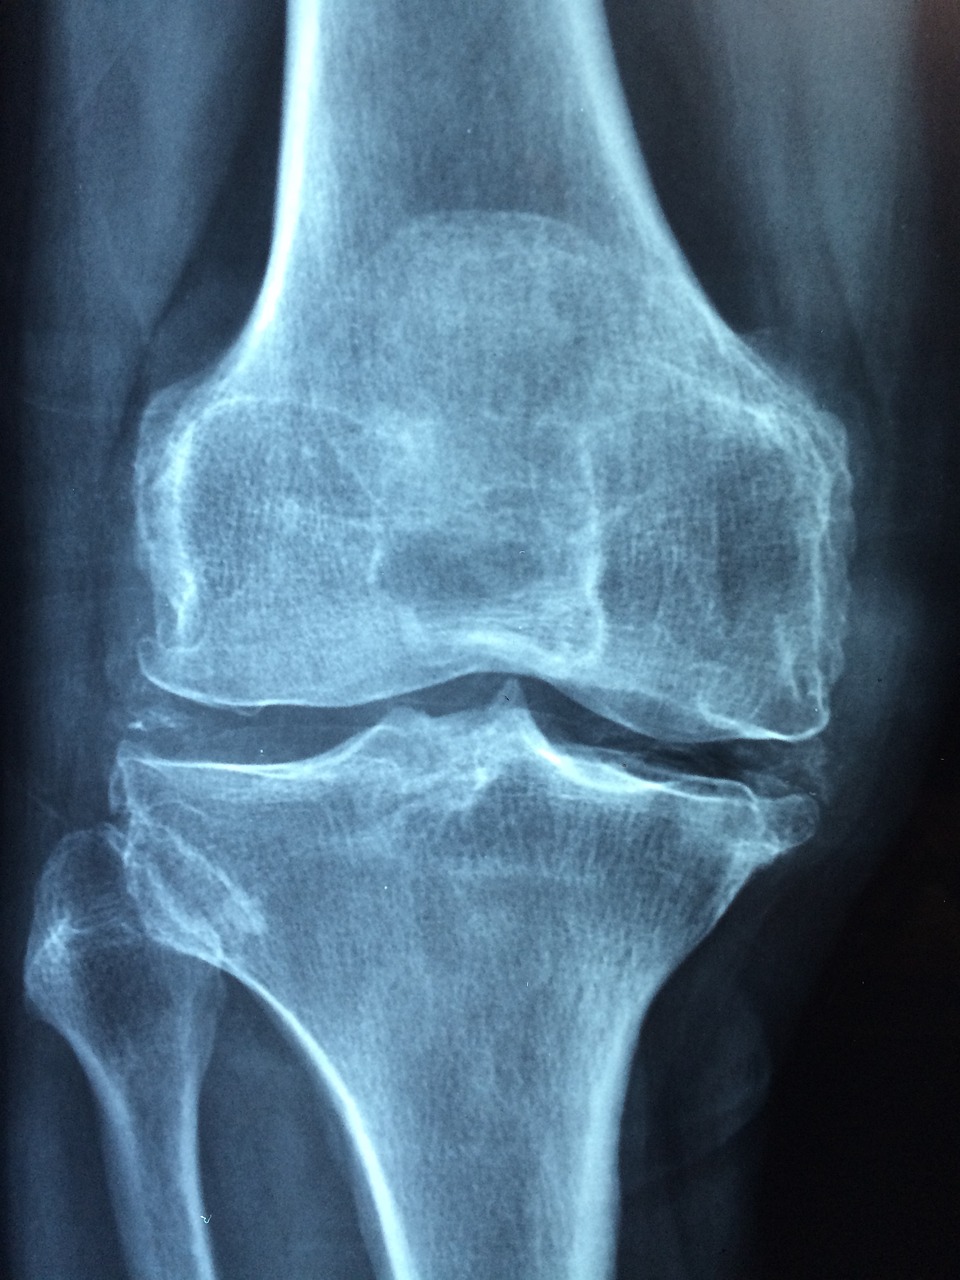

Сустав представляет собой подвижное соединение, которое состоит из костей, мышц, хрящей, связок и соединительной ткани. В совокупности все эти составляющие облегчают скольжение костных поверхностей и приводят сустав в движение.

У пожилых пациентов боль часто характеризуется отложением солей или разрушением хряща, что сочетается с разрастанием костной ткани.